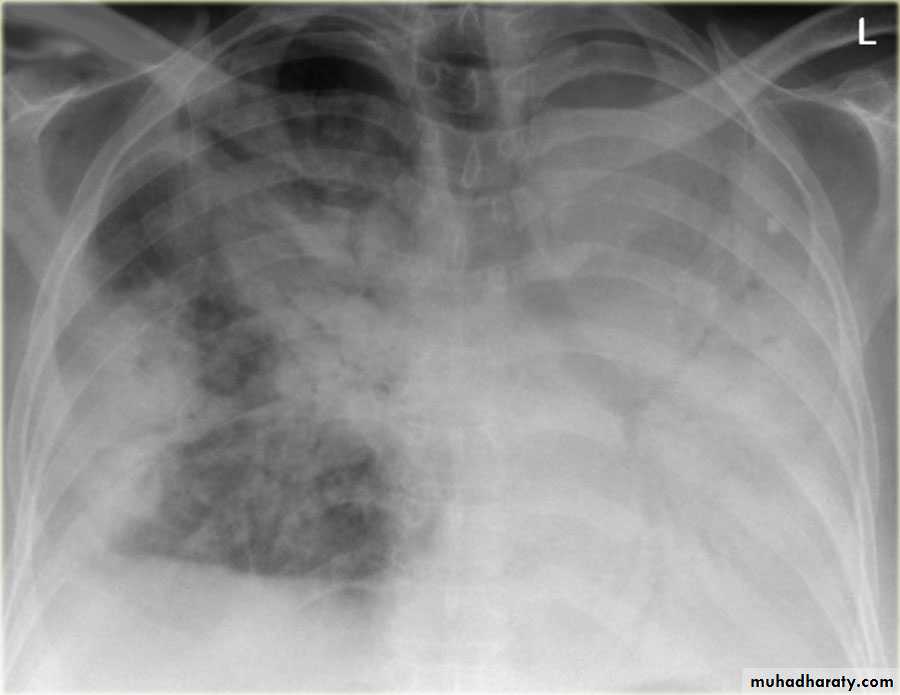

Patient with fever, rigor and dyspnea